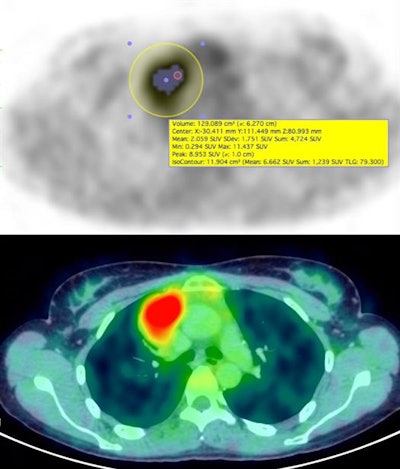

To determine the efficacy of quantification parameters, researchers used a fixed threshold segmentation method with a maximum standard uptake value (SUVmax) of 41%, as recommended by the European Association of Nuclear Medicine (EANM). From that point, the researchers calculated SUVmax, peak SUV, mean SUV, metabolic tumor volume, and total lesion glycolysis (TLG) at all three PET scan time points.

A further analysis of PET parameters discovered which variables were most effective in predicting event-free survival. For example, a multivariate analysis revealed that positive predictive value was the only statistically significant factor in determining event-free survival with a hazard ratio of 1.07 (1.0 to 1.15, p = 0.00008).

Based on the Cox regression model, metabolic tumor volume and SUVmean based on the third PET scan were most statistically significant in event-free survival. Metabolic tumor volume recorded a hazard ratios of 1.07 (1.0 to 1.13, p = 0.005, while SUVmean registered a hazard ratio of 2.0 (1.4 to 2.82, p = 0.0001).